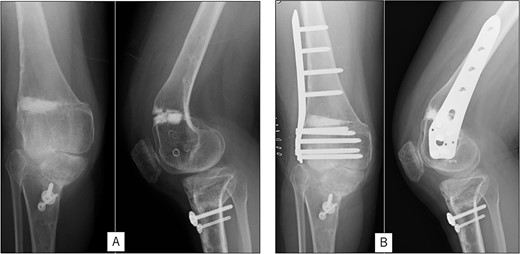

A 23-year-old woman presented with bilateral knee pain and gait abnormalities owing to marked lower extremity deformity. She was diagnosed with EVC as a child but had never been followed up by orthopedics because she was not in pain. On physical examination, marked valgus instability was observed in both knees, and the motion of both knees ranged from 10° to 135°. Radiographic examinations of both knees, including computed tomography, showed valgus deformity, lateral and anterior depression of the proximal lateral tibial plateau, and external rotation deformity of the lower leg. Patellar dislocation was observed in the right knee (Fig. 1). The radiological angles are presented in Table 1. The right knee underwent surgery first, followed by the left 10 months later. Lateral and medial skin incisions were made. Extensive lateral retinacular release, fractional lengthening of the distal lateral hamstring, and Z-lengthening of the iliotibial band were then performed. At this stage, peroneal nerve strain was identified, and decompression of the peroneal nerve was performed. Osteotomy was subsequently performed on the tibia. Closed-wedge varus and derotational osteotomy of the proximal tibia and open-wedge varus osteotomy of the distal femoral varus were performed. In addition, vastus medialis advancement was performed on the right knee, and patellar realignment was achieved in extension (Fig. 2). However, the knee showed a subluxation tendency owing to flexion of >30°; therefore, the postoperative rehabilitation plan progressed more slowly than that of the left knee. Range of motion training began on the left knee immediately after surgery without any restrictions, but on the right knee only after 3 weeks of postoperative immobilization in the extended position. However, ambulation exercise was performed on both knees with no loading for 3 weeks, then partial loading was initiated, and full loading was permitted at 8 weeks postoperatively. Early postoperative standing radiography showed residual mild valgus deformity of the lower limbs (Fig. 2, Table 2). In addition, the right knee showed patellar re-dislocation 2 months postoperatively, and the patellar deformity gradually progressed owing to the femoral implant; therefore, the patient underwent implant removal, tibial tubercle transfer, and medial patellofemoral ligament reconstruction 1.5 years after the initial surgery (Fig. 3). Six months later, she fell while walking and developed a fracture at the osteotomy of the right femur; open reduction and internal fixation were performed (Fig. 4). The remaining years passed uneventfully, and 10 years after the initial surgery, the patient still had mild valgus deformity of the lower limbs, but had no recurrence other than that experienced immediately after surgery, no complaints of knee pain, and a stable gait (Fig. 5, Table 2).

Postoperative radiography: (A) immediate postoperative radiograph of the right knee, (B) immediate postoperative radiograph of the left knee, (C) the entire lower limbs at 2 months after left knee surgery. Mild valgus deformity of the lower limbs persisted.